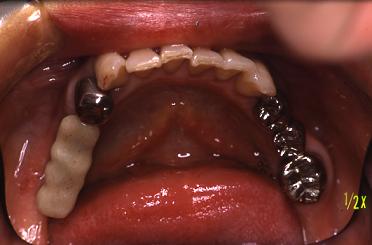

インプラントを4本植めました

(術直後)

仮り歯を入れました

冠が入りました